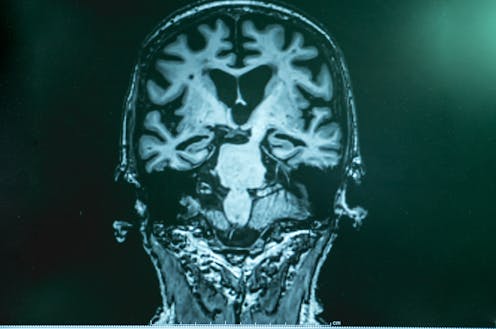

Alzheimer’s disease is caused by presence of two abnormally folded proteins: amyloid and tau. There is increasing evidence[7] these proteins spread in the brain in a similar way to prion diseases[8]. So the mode of transmission the authors propose is certainly plausible.

However, given the amyloid protein deposits in the brain at least 20 years[9] before clinical Alzheimer’s disease develops, there is likely to be a considerable time lag before cases that might arise from the receipt of donated hGH become evident.